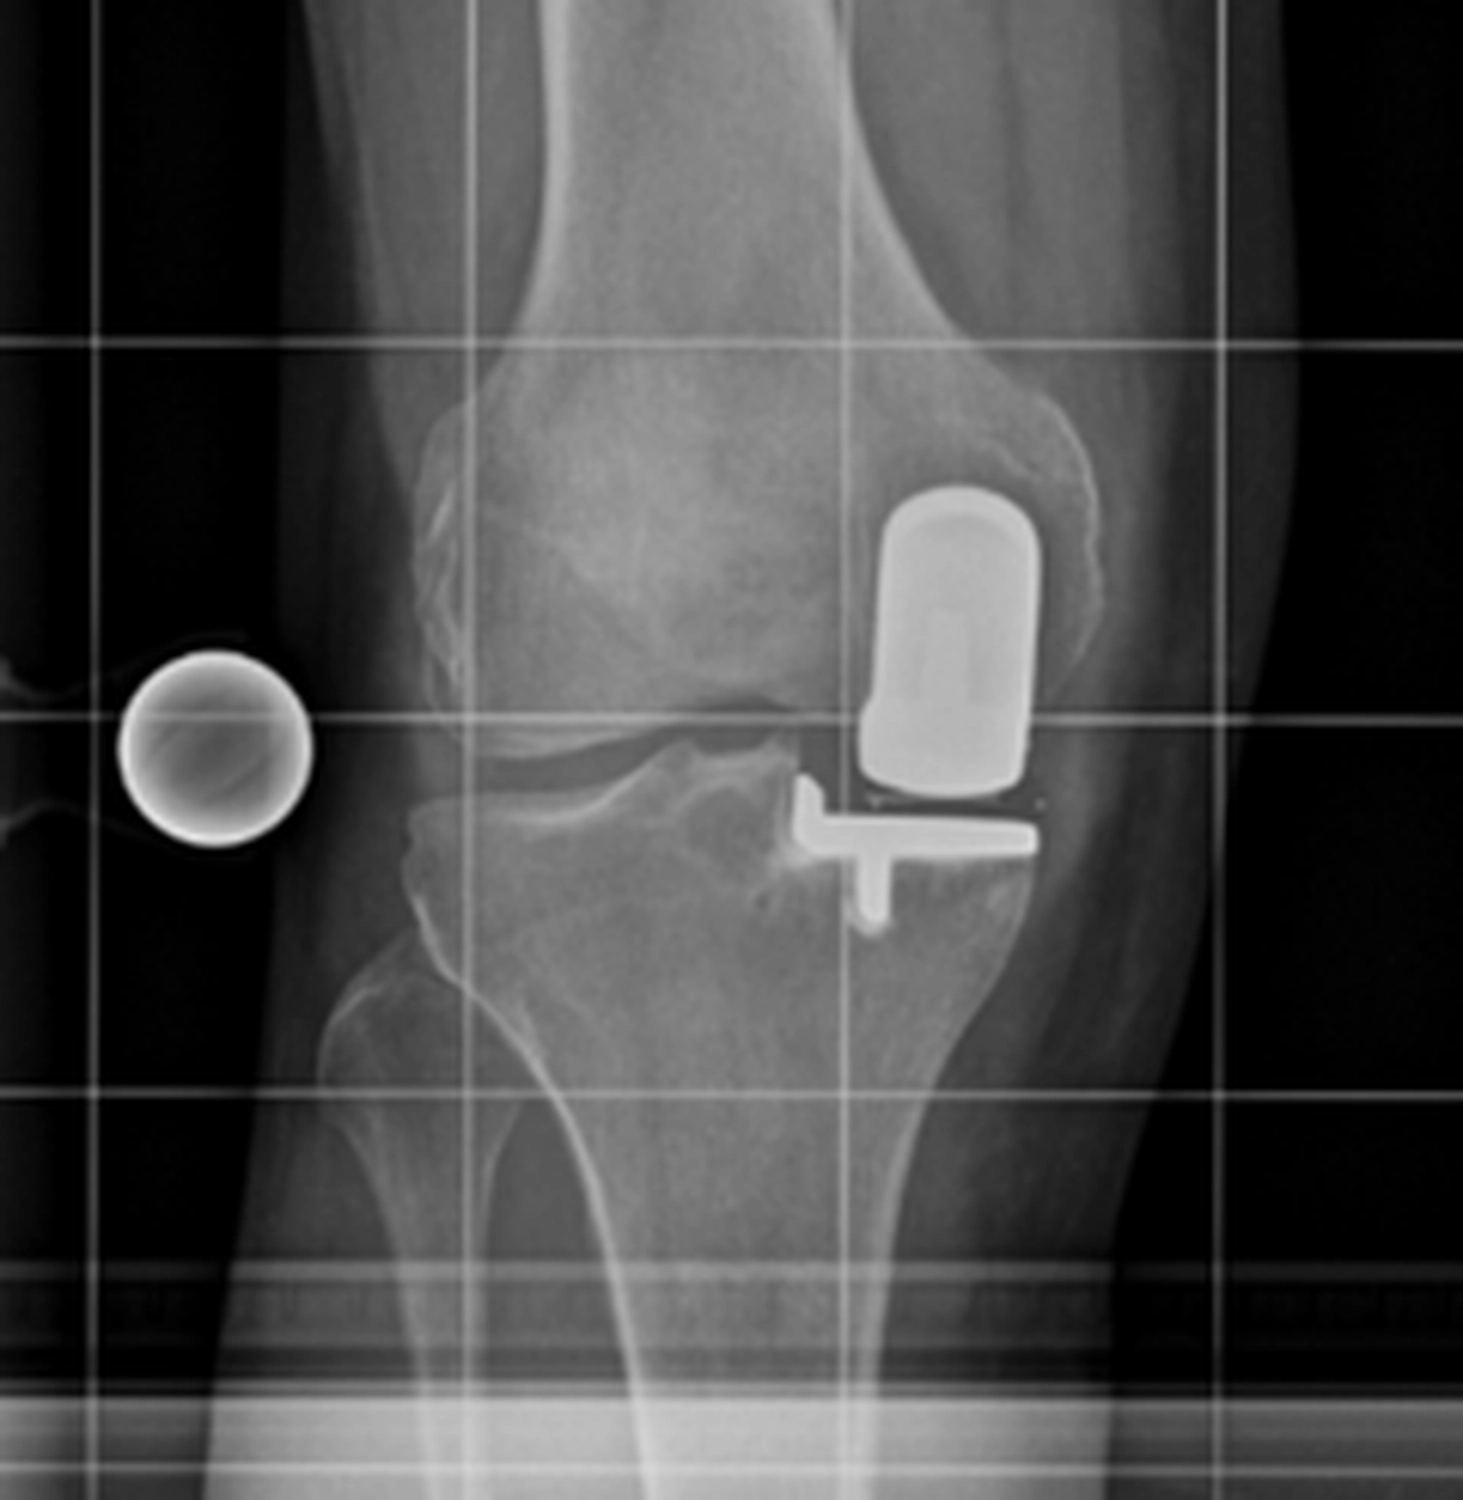

Bei der Implantation einer Knieprothese werden die zerstörten Gelenkflächen des Oberschenkel- und Schienbeinknochens millimetergenau entfernt und durch passgenaue Metallkomponenten ersetzt.

Dazwischen liegt ein hochbelastbares Kunststoffinlay, das die Gleitfläche bildet.

Je nach Schädigung und Gelenkzustand werden unterschiedliche Prothesenarten verwendet:

Bei der Implantation einer Knieprothese werden die zerstörten Gelenkflächen des Oberschenkel- und Schienbeinknochens millimetergenau entfernt und durch passgenaue Metallkomponenten ersetzt. Dazwischen liegt ein hochbelastbares Kunststoffinlay, dass die Gleitfläche bildet.

Die Operation dauert etwa 60 bis 90 Minuten und erfolgt unter Voll- oder Spinalanästhesie.